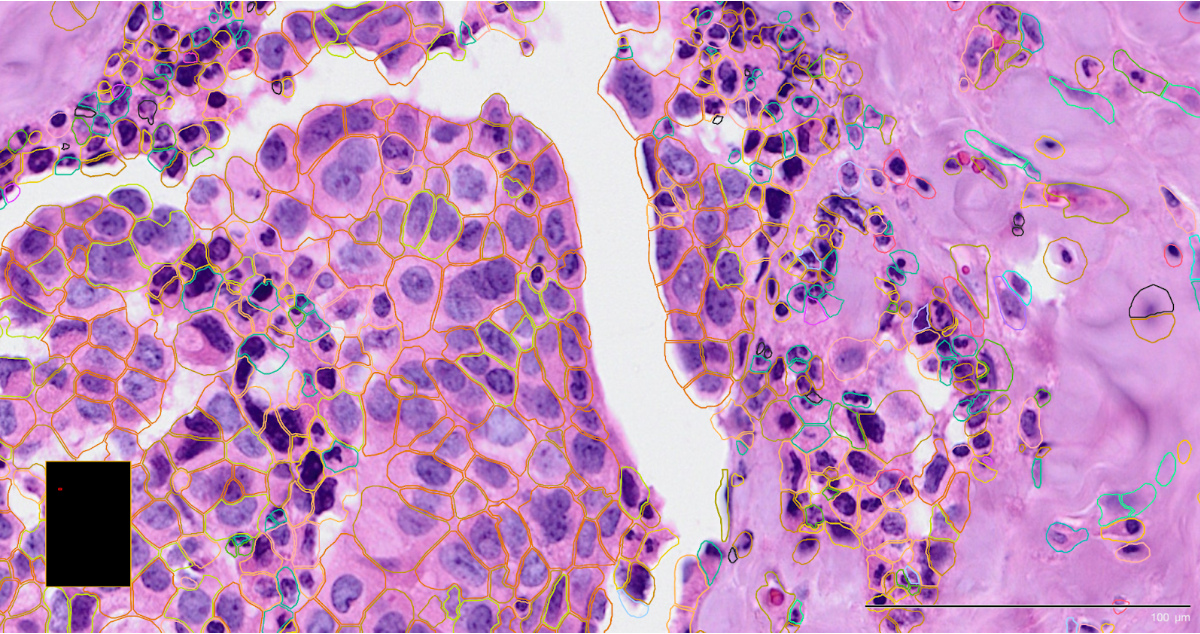

Cell segmentation is the computational step in imaging-based ST that identifies the boundaries of individual cells so that RNA molecules can be correctly assigned to each one. These utilise the stained images to identify cell border shapes that are necessary for cell-level analyses downstream.

The following images are of Xenium using two different staining approaches, H&E and immunofluorescent respectively, with the detected cell boundaries overlayed on both.

The H&E stain is often conducted as part of im-SRT protocols and is used to determine basic cell lineages from the morphology. In CosMx, this is often used to preview the slide for FOV selection.

The immunoflourescent stain demarcates more specific subcellular components. This stain is often used in the automated on-machine cell segmentation step.

Accurate segmentation is essential because it determines how reliably transcripts are assigned to individual cells, which directly affects downstream analyses. Commercial platforms like CosMx and Xenium include on-machine segmentation.